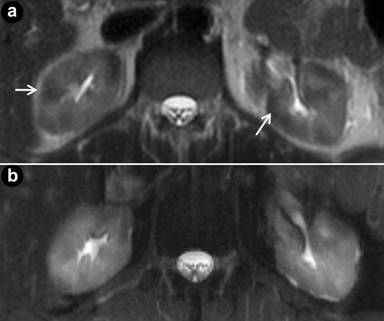

MRI demonstrated diffuse pancreatic enlargement which was hypoenhancing on T1-weighted images. There was a smooth stricture in the distal common bile duct. There were also wedge shaped regions of T2 hypointensity and decreased renal enhancement bilaterally with apparent diffusion coefficient (ADC) values of 1.027 x10-3 mm/sec2 in right kidney (compared to an ADC value of 2.040 x10-3 mm/sec2 in adjacent normal renal parenchyma) and 1.065 x10-3 mm/sec2 in left (compared to an ADC value of 1.940 x10-3 mm/sec2 in adjacent normal renal parenchyma). There was no peripancreatic edema on pretreatment MRI. The imaging findings, like the CT findings, were suggestive of autoimmune pancreatitis (Figure 2).

Figure 2. Pre-treatment (a.) and post-treatment (b.) T2-weighted axial images through the kidneys. Pre-treatment T2 weighted images demonstrate areas of decreased signal intensity (arrows) representing renal manifestations of autoimmune pancreatitis. |